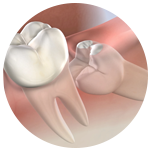

Extracción de Cordales

Realizamos la extracción de muelas del juicio de forma segura, evitando dolor, infecciones y problemas de alineación.